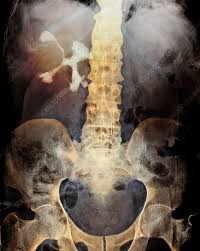

Kidney Stone X Ray Cost. 20 years experience radiology. When the stone is not on the focus the sound waves can damage the soft tissue of the kidney.

Ct kub ct scan kub kidney ureter bladder is ct scan of urinary system. Case studies case 1. Those kidney stones that are not visible on an x ray are usually detected on a ct scan.

Kidney stone cost 12k includes anesthesia laser work stent amount. Can u see kidney stones on x ray. My out of pocket costs were insignificant because my copays have always been very small. Those kidney stones that are not visible on an x ray are usually detected on a ct scan.